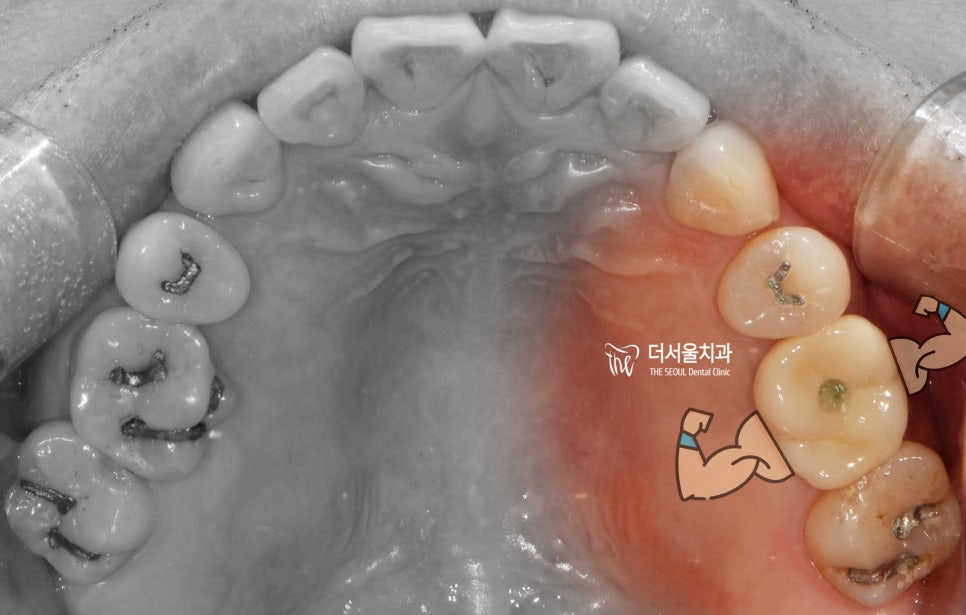

『지연식립』

앞서 상악동거상술 및 뼈이식이 진행되었다

말씀을 드렸는데 이 분의 경우

bone defect 이라 하여 골 위축이

상당히 많이 진행되었었기 때문에

바로 임플란트를 심을 수 있는

상황이였음에도 조금 지연시켜서

뼈가 더 단단히 굳게 한 뒤에

임플란트 시술을 진행했었습니다.

2보 전진을 하려, 1보 후퇴를 하거죠.

그렇게 대략, 3~4개월 가량이

소요되었던 거 같습니다.